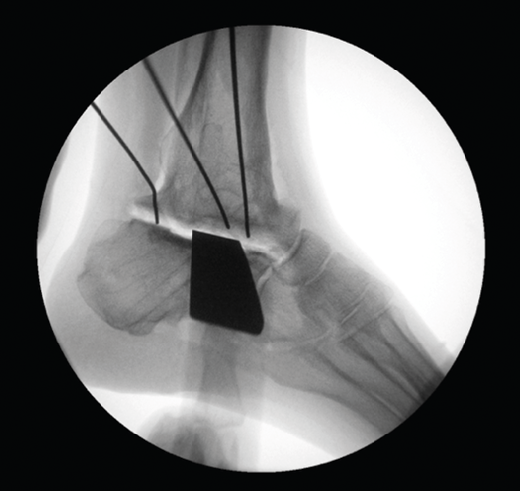

Caso 2. Coalición tarsal

Se trata de un caso de Dr. Sobrón, publicado en Foot Ankle International(9), que presenta a un paciente varón de 17 años con pie plano valgo doloroso. Tras la valoración clínica y radiológica, se observa una coalición astragalocalcánea (Figura 6).

Utilidad de la impresión 3D: se decidió imprimir una guía 3D de corte como ayuda intraoperatoria. La guía permite la resección de la coalición de manera completa y reducir la necesidad de guía con fluoroscopia.

Pasos:

- Obtención de las imágenes.

- Diseño de la guía de corte guiada por aguja de Kirschner (Figura 7).

- Esterilización con gas.

- Resección intraoperatoria (Figura 8).